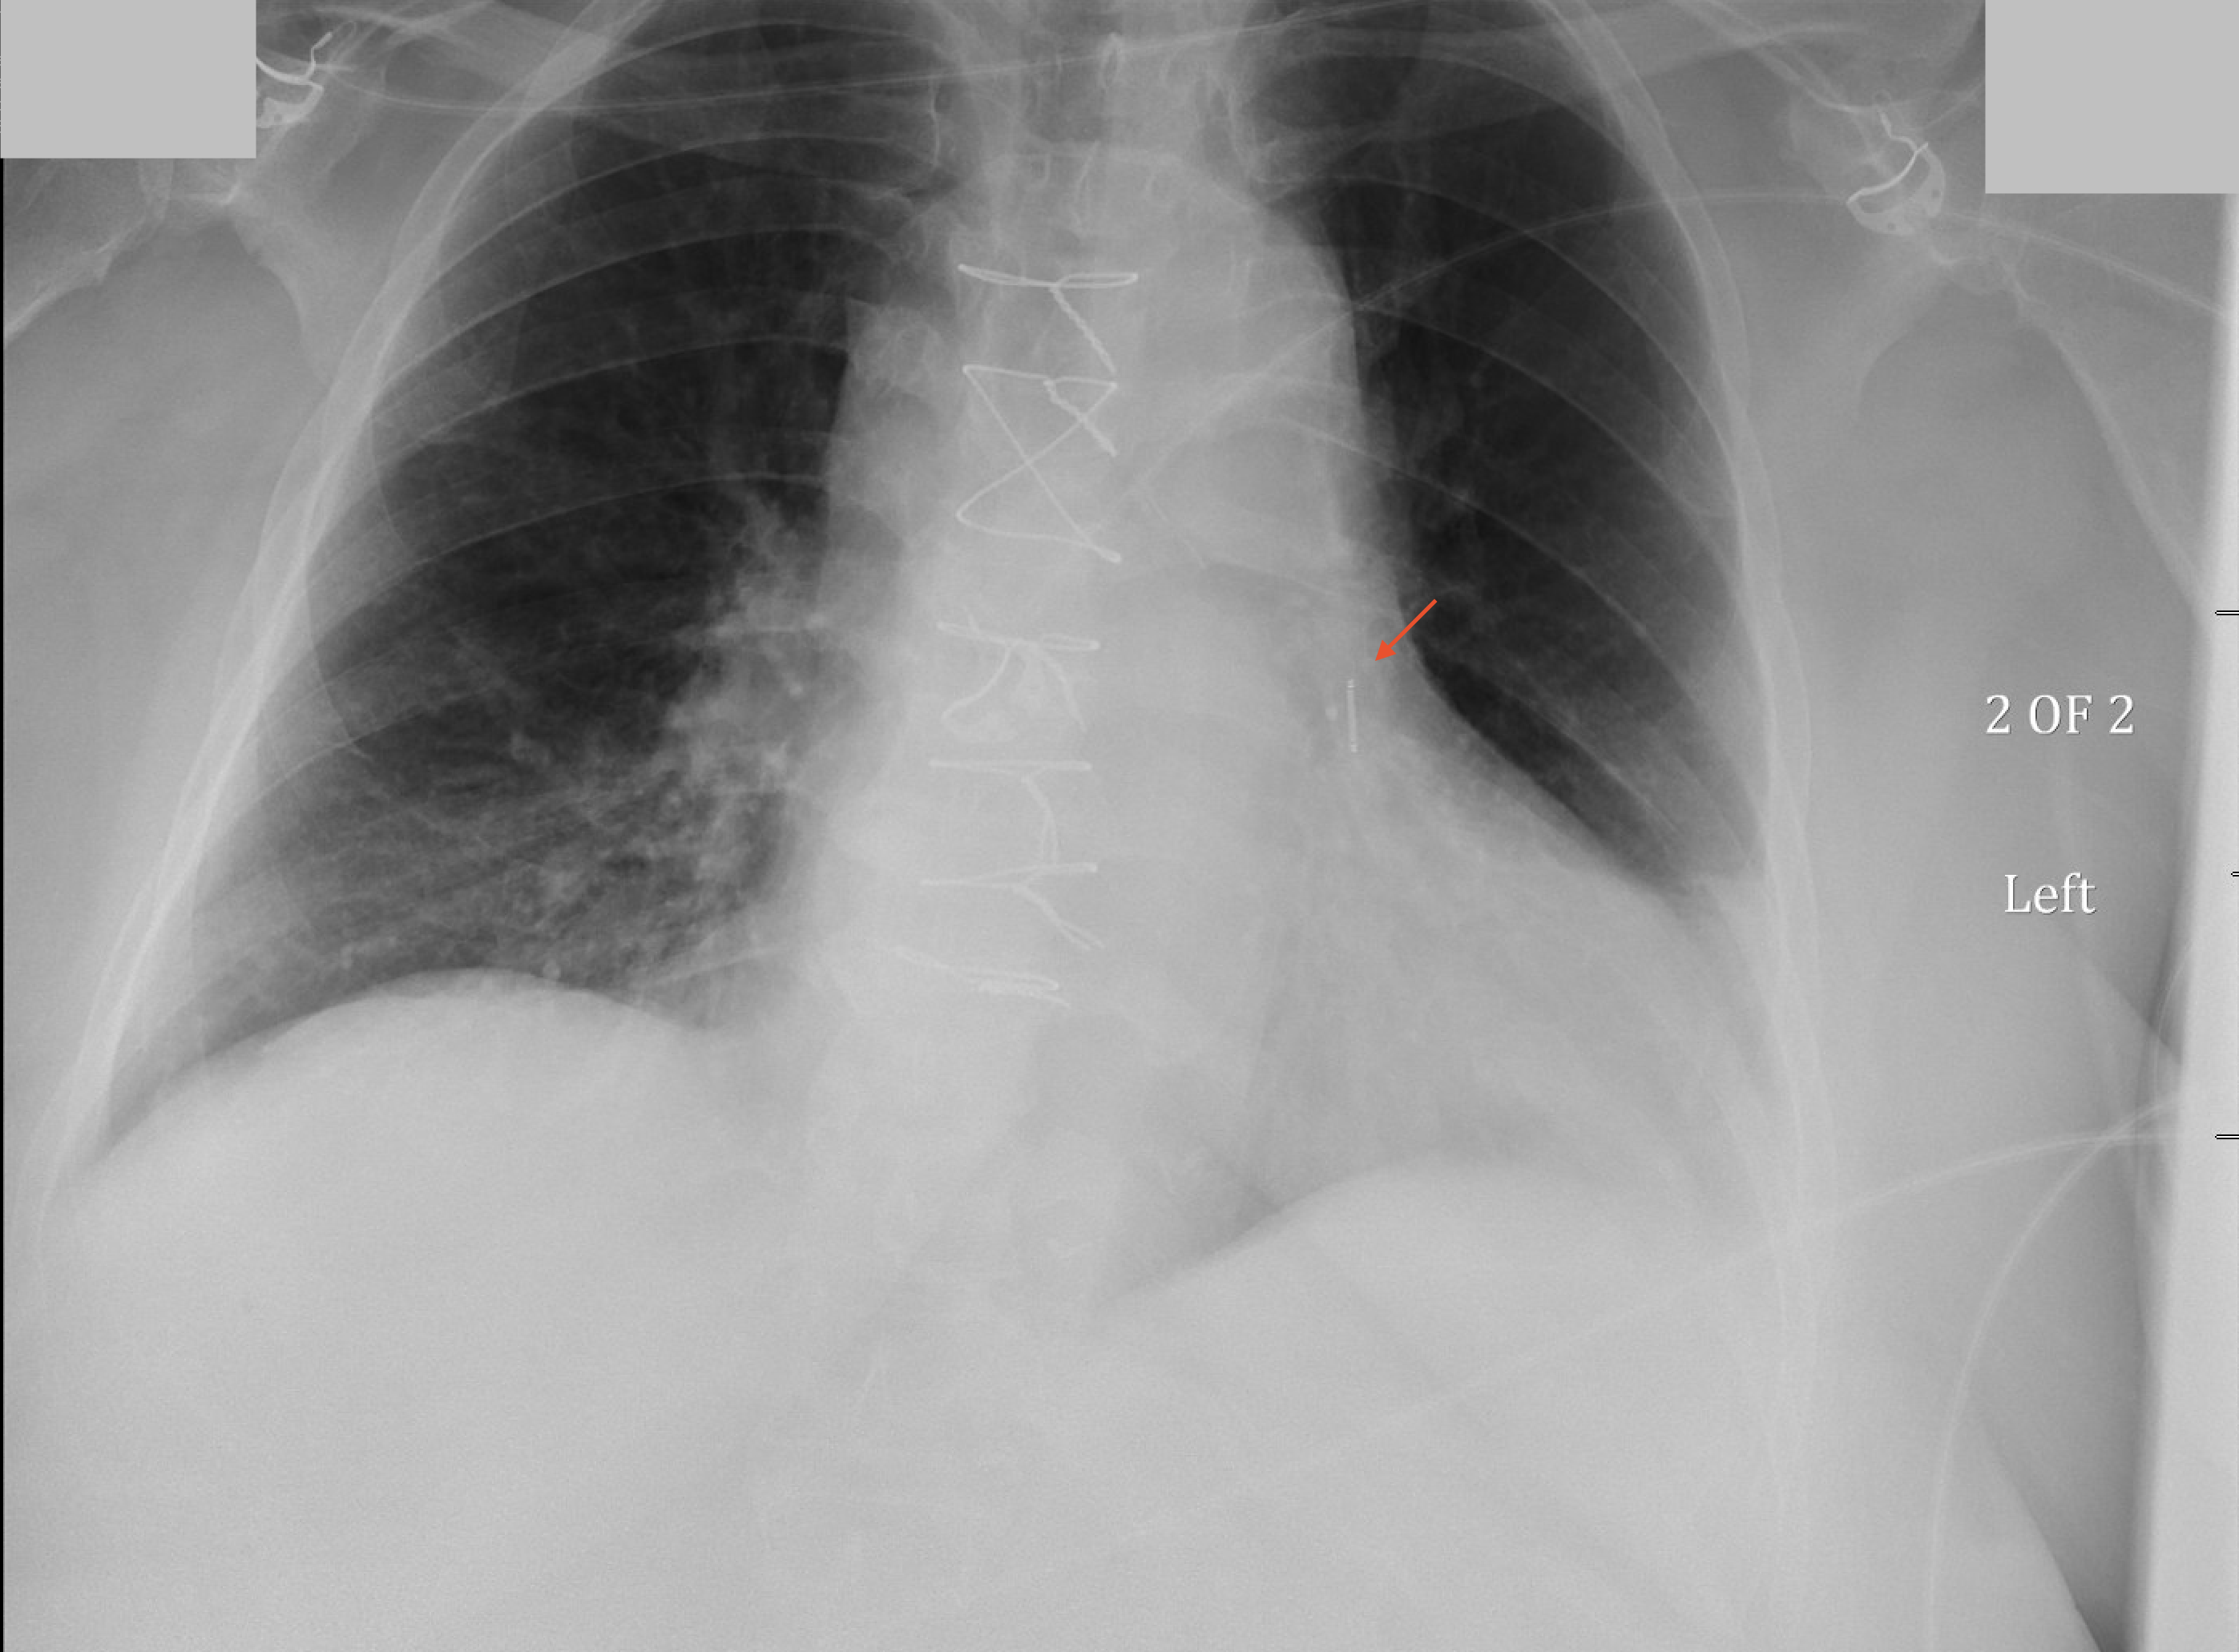

Radiographic Appearance

Note the Presence of the CardioMEMS Superimposed Over the Left Pulmonary Artery in the Following Chest X-Ray (and Inset)